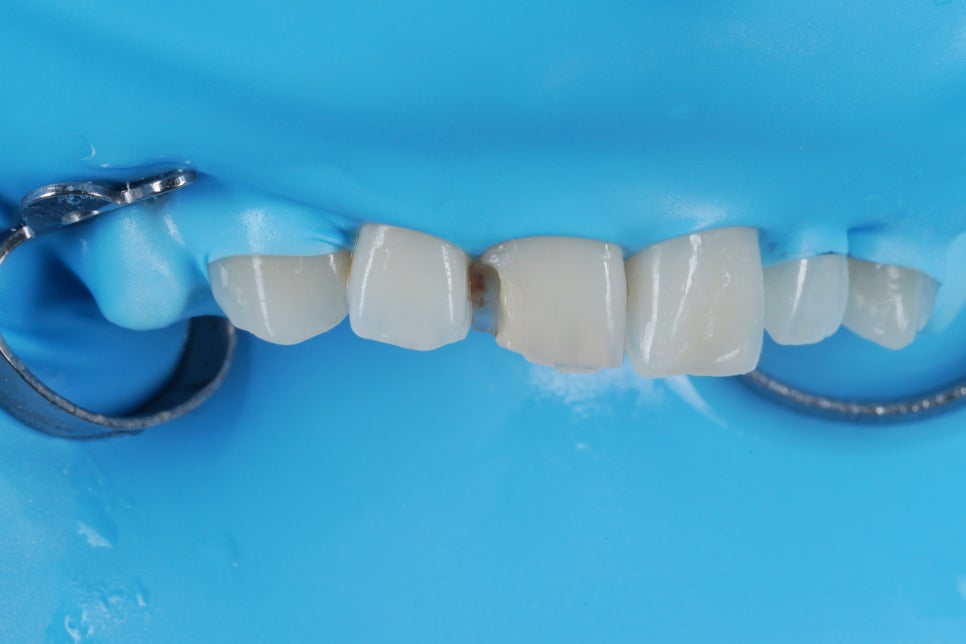

기존 레진은 이미 오염되어서

못쓰는 상태에 이르렀습니다.

이렇게

<러버댐>이라는 재료를 이용해서

때울 부위를 구강내와 격리하는

사전작업이 필요한 이유입니다.

침과 피, 구강내 습기로부터

격리되지 않은 부위는

언제든 이렇게 오염될 수 있습니다.

레진(Composite)은 세라믹에 비하면

변색에 취약한 재료인만큼

치료과정에서

방습과 격리를 잘 해야 합니다.

방습과 격리가 잘 된 레진은

세라믹과 그 수명이 크게 다르지 않습니다.